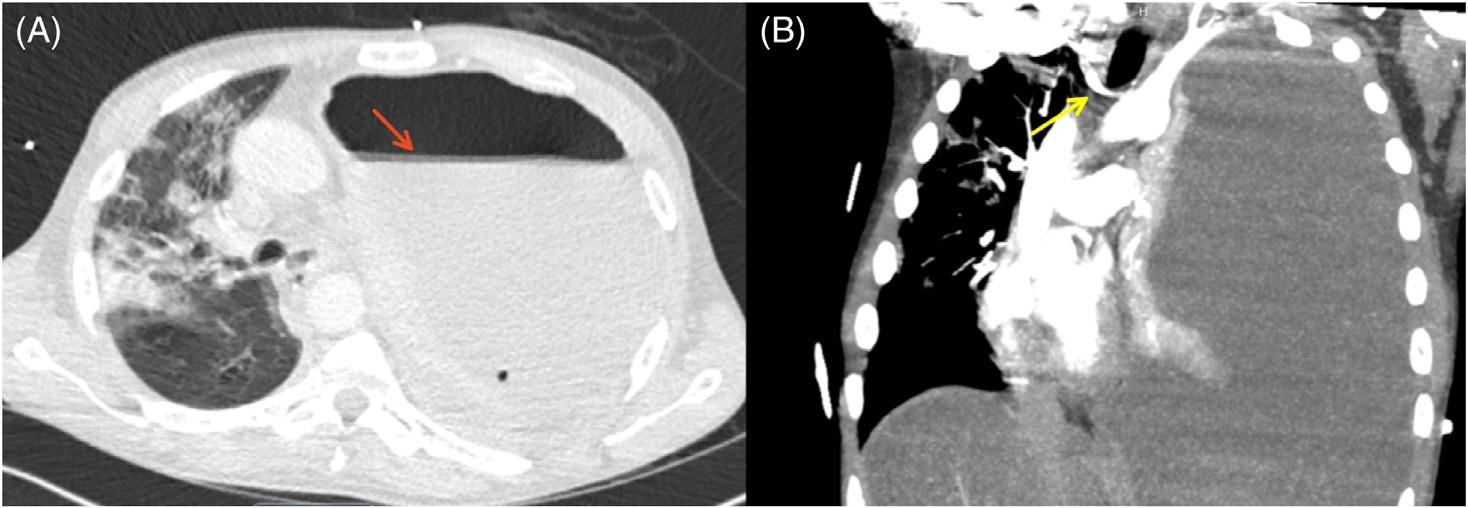

Emergentcomputedtomographyoftheabdomenand pelvisrevealedalargeleftretroperitonealandperitoneal hematomasecondarytoleftRAArupture,aswellasconcern fordevelopingsplenicinfarctsintheleftlowerrenalpole (Image).Thepatientwastakenemergentlytotheoperating room(OR)forexploratorylaparotomywithintwohoursof EDarrival.Sheunderwentsuprarenalcross-clampingwith repairoftheleftrenalarteryandligationofrenalvessels.She returnedtotheORtwodayslaterforleftnephrectomyand abdominalclosure.Shewasextubatedandtransferredtothe floor.Shewasdischargedhometwodayslaterin goodcondition.

Introduction: Renalarteryaneurysmruptureisararebutmorbiddiagnosis,oftenrequiringemergency surgeryandnephrectomy.Clinicalpresentationcanmimicmorecommonpathologyinnon-pregnant womensuchasrupturedovariancyst.

CaseReport: Wepresentacaseofawomanwithapriorhistoryofovariancystpresentingwitha rupturedrenalarteryaneurysm.Promptcomputedtomography(CT)imagingrevealedaleftrenalartery aneurysmrupturewithhemoperitoneumandrenalinfarct.Sheunderwentemergencylaparotomyand nephrectomyandwasultimatelydischargedingoodcondition.

Conclusion: Whileovariancystruptureisthemostcommoncauseofspontaneoushemoperitoneumin non-pregnantwomenofchildbearingage,renalarteryaneurysmruptureshouldbeconsideredand promptCTimagingobtained,particularlyincasesofhemodynamicinstability,toensureprompt treatment.[ClinPractCasesEmergMed.2024;8(3)194–196.]